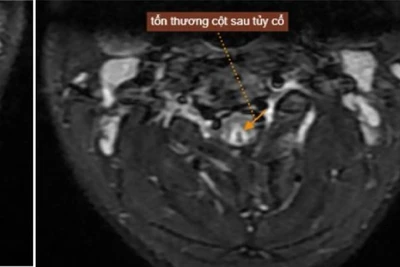

Hình ảnh tổn thương tủy sống trên bệnh nhân ngộ độc khí N2O.

Vợ anh, chị H. cũng xuất hiện triệu chứng tương tự: Tê bì hai bàn chân, cảm giác “như kiến bò trong người”, đi lại loạng choạng. Đến khi vào Trung tâm Chống độc, bác sĩ kết luận cả hai tổn thương tủy sống cổ do ngộ độc khí N₂O, ảnh hưởng đến dây thần kinh vận động và cảm giác.

Có bệnh nhân chỉ mới 20 tuổi, sau vài tháng dùng bóng cười đã phải nhập viện vì liệt tứ chi. Chụp MRI cho thấy tổn thương tủy sống không thể hồi phục.